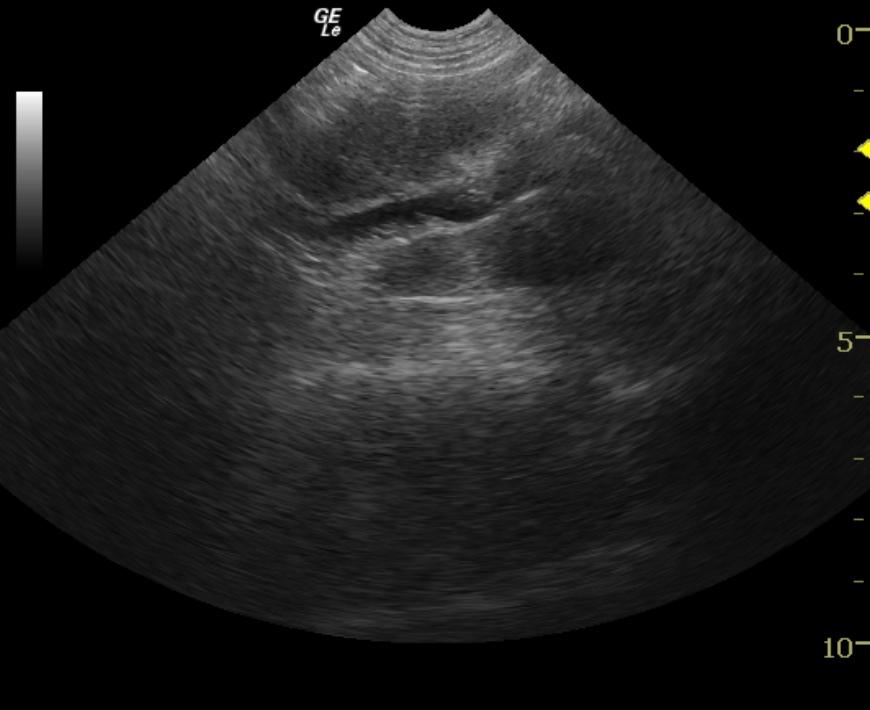

An 11-year-old FS Jack Russell Terrier dog with history of MCT – grade II on the foot in 1999 and grade I on the skin in 2004, was presented for pruritus near the base of tail. The only significant finding on physical examination was a 1.5 cm ulcerated mass in the right ventral anal mucosa. Eosinopenia and elevated MCV and MCHC were evident on CBC. The mass was surgical excised and the patient treated with antibiotics. Biopsy results showed a grade II MCT. The patient was presented three months later for recurrence of the anal mass. Abdominal ultrasound was advised prior to further surgery.